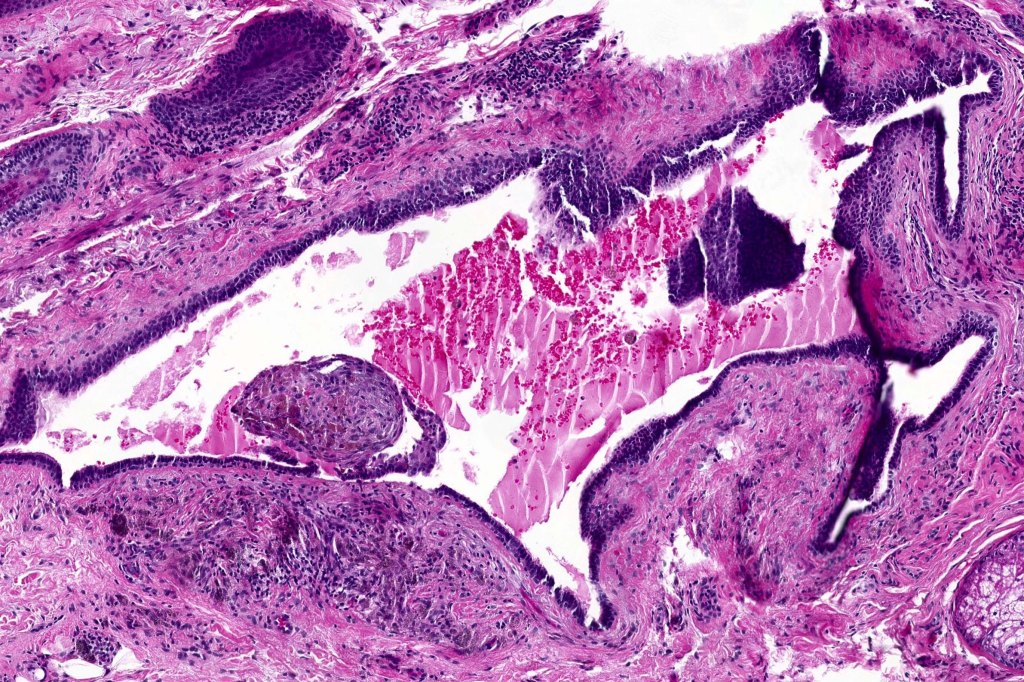

Histological features

•Pseudo-encapsulated unilocular or multilocular

•Outer myoepithelial cells & inner layer of columnar cells with eosinophilic cytoplasm showing decapitation secretion

•Adenomatous/papillary component (cystadenoma)